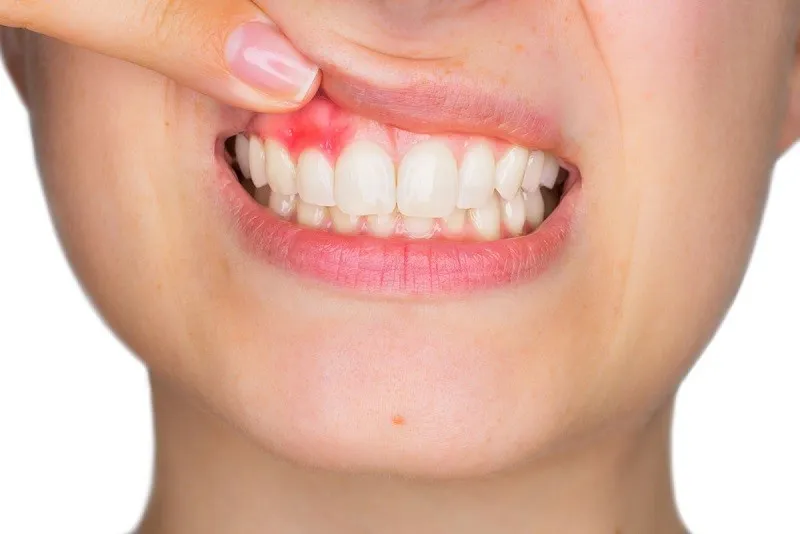

nú răng bị chảy máu là một triệu chứng phổ biến mà nhiều người gặp phải trong sinh hoạt hàng ngày, đặc biệt khi đánh răng hoặc

Sưng lợi là tình trạng phổ biến mà nhiều người gặp phải trong cuộc sống hàng ngày. Đây không chỉ gây đau nhức và khó chịu mà

Nướu sưng (hay còn gọi là sưng lợi) là một tình trạng răng miệng khá phổ biến, gây ra không ít phiền toái và đau nhức cho